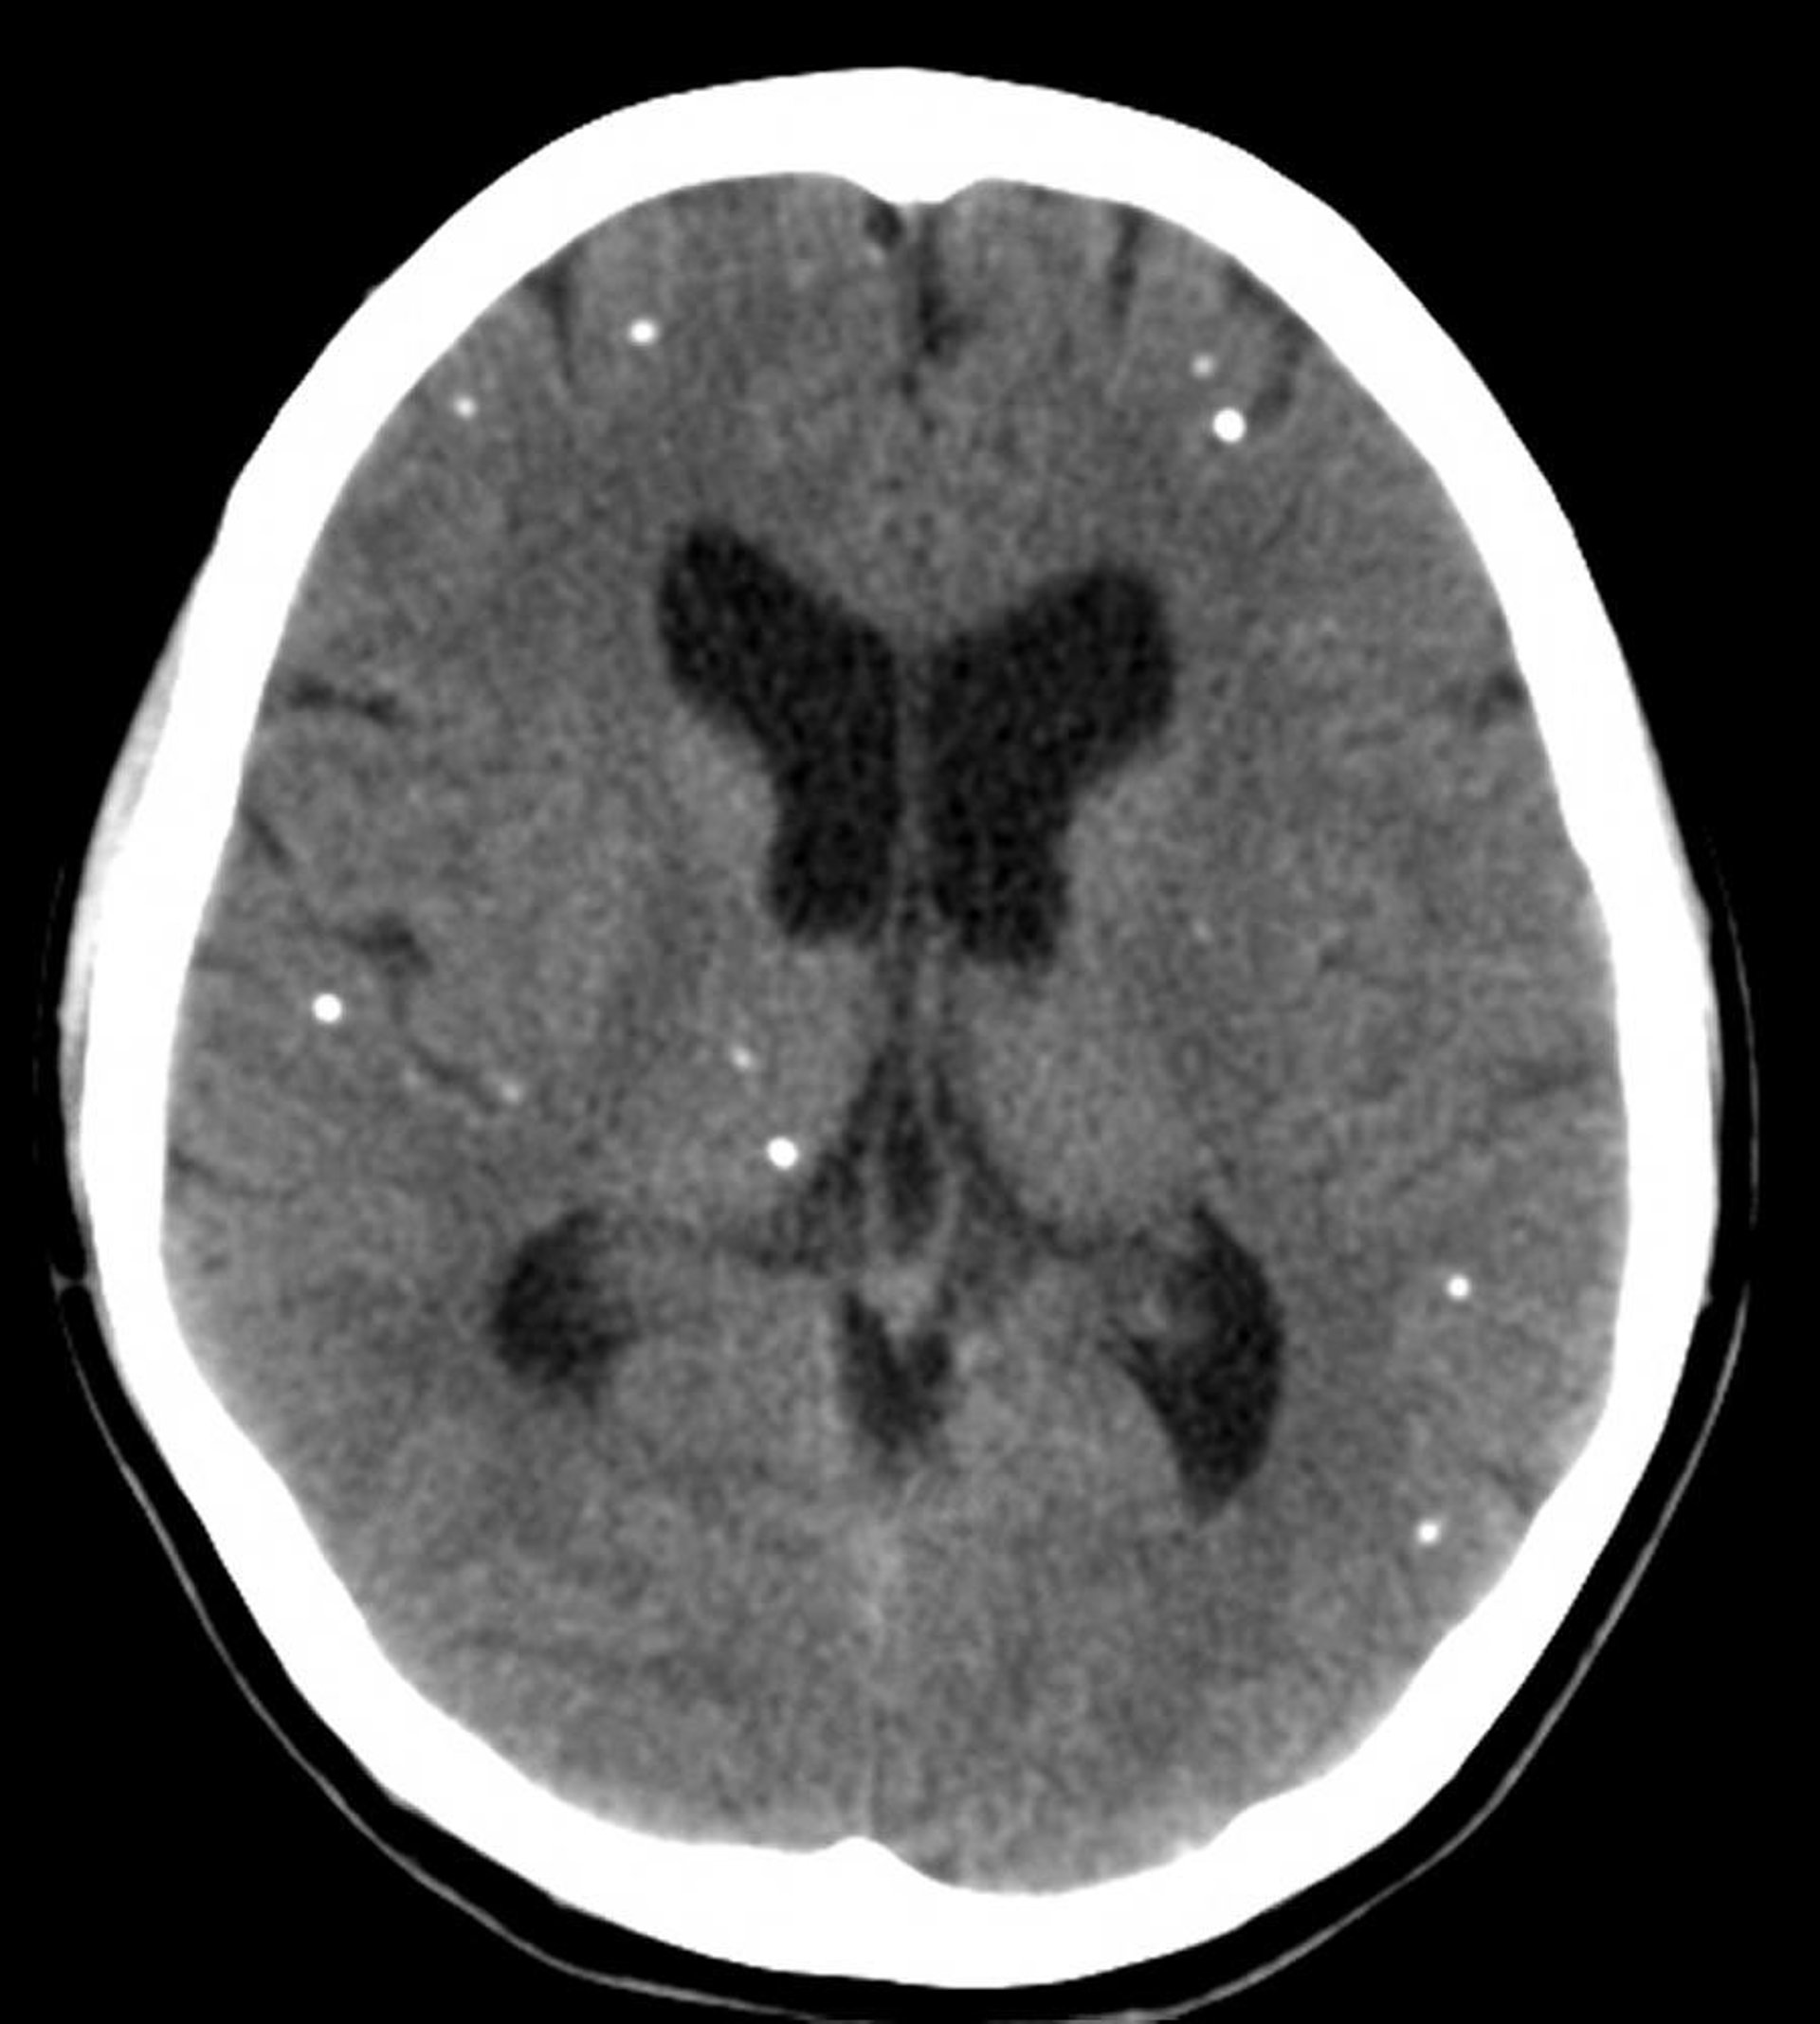

Neurocysticercosis is suspected in patients who live in or have come from developing countries and who have eosinophilic meningitis or unexplained seizures, cognitive or focal deficits, or personality changes. It is suggested by multiple calcified cystic lesions seen on CT or MRI; a contrast agent may enhance the lesions. Diagnosis requires serum and CSF serologic tests and occasionally cyst biopsy.